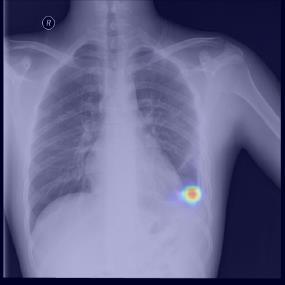

Chest X-ray (CXR) is the most typical diagnostic X-ray examination for screening various thoracic diseases. Automatically localizing lesions from CXR is promising for alleviating radiologists' reading burden. However, CXR datasets are often with massive image-level annotations and scarce lesion-level annotations, and more often, without annotations. Thus far, unifying different supervision granularities to develop thoracic disease detection algorithms has not been comprehensively addressed. In this paper, we present OXnet, the first deep omni-supervised thoracic disease detection network to our best knowledge that uses as much available supervision as possible for CXR diagnosis. We first introduce supervised learning via a one-stage detection model. Then, we inject a global classification head to the detection model and propose dual attention alignment to guide the global gradient to the local detection branch, which enables learning lesion detection from image-level annotations. We also impose intra-class compactness and inter-class separability with global prototype alignment to further enhance the global information learning. Moreover, we leverage a soft focal loss to distill the soft pseudo-labels of unlabeled data generated by a teacher model. Extensive experiments on a large-scale chest X-ray dataset show the proposed OXnet outperforms competitive methods with significant margins. Further, we investigate omni-supervision under various annotation granularities and corroborate OXnet is a promising choice to mitigate the plight of annotation shortage for medical image diagnosis.